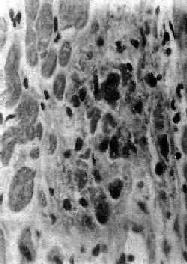

Aschoff 小体体积颇小,一般显微镜下才能看见(图8-19),多发生于心肌间质、心内膜下和皮下结缔组织;心外膜、关节和血管等处少见。在心肌间质内者多位于小血管旁,略带圆形或梭形,其中心部为纤维素样坏死灶,周围有各种细胞成分:①Anitschkow细胞:胞浆丰富,嗜碱性,核大,呈卵圆形、空泡状。染色质集中于核的中央,核的横切面状似枭眼;纵切面上,染色质状如毛虫。②Aschoff巨细胞(Aschoff giant cell):含有1~4个泡状的核,与Anitschkow细胞相似,胞浆嗜碱性。以上两种细胞的来源尚有争论,但现代标记技术证明其为巨噬细胞源性。③小体内还有少量淋巴细胞(主要为T细胞)和个别中性粒细胞。此期经过约2~3个月。

图8-19 Aschoff小体

主由Anitschkow细胞、Aschoff巨细胞和淋巴细胞等组成,中心部常有纤维素样坏死物